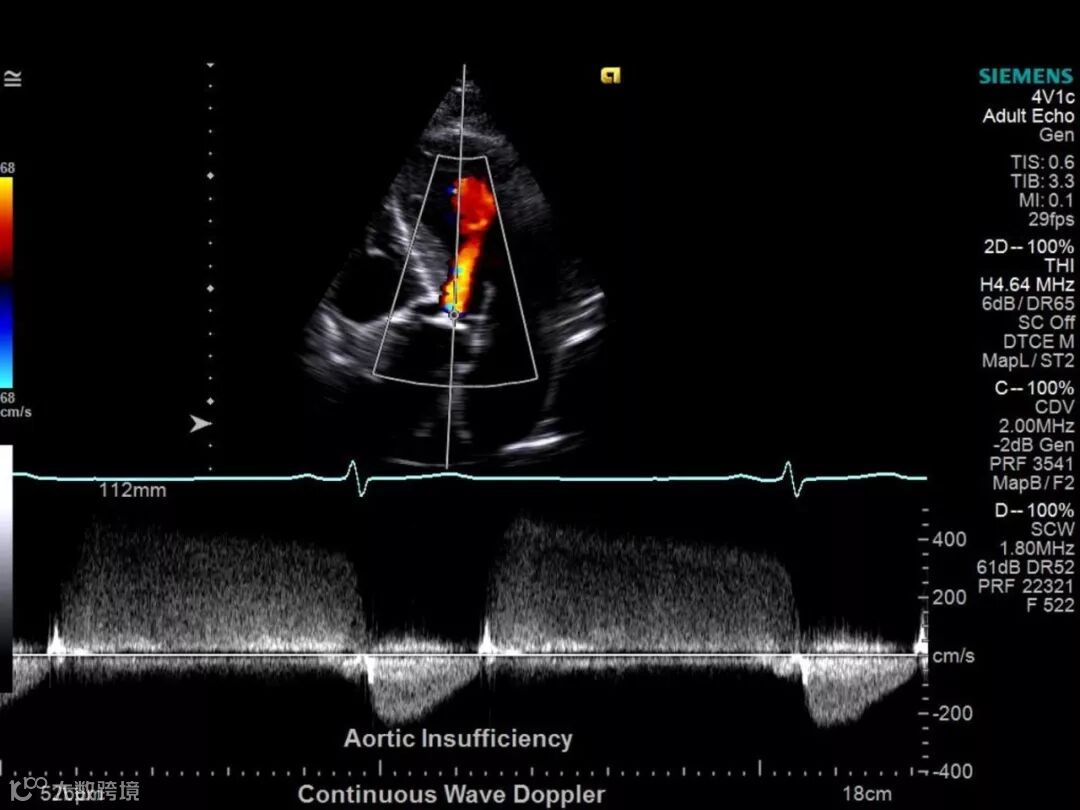

2001年,西门子收购美国超声巨头ACUSON公司,建立全新的ACUSON超声产品线,原有SONOLINE系列超声逐步退出市场,西门子通过美中互利和蓝韵布局中国市场,美中互利为其国内中高端彩超代理,蓝韵代理西门子的X150(2007年)低端彩超。

根据西门子医疗招股说明书,西门子医疗包含三大业务,分别为影像、治疗和诊断,其中影像收入占比最大,2017年影像收入占比为59%,年收入达到82亿欧元,其中超声占比为7%,约为5.75亿欧元,折合6.56亿美元。

曾经在中国彩超市场的G.P.S,P和S之间的差距并不大,到现在却已成为G.P…..S了。从产品端来看,西门子的彩超无论从高端技术层面,还是产品线的丰富程度都处于第一梯队,但是在中国市场却一直在下滑,行业内普遍对于公司前景颇为悲观。西门子中国超声业务目前依然处于2014年压库存爆仓事件的影响的阴影中。同时人员流失较多,超声业务负责人频频变动,甚至一些并无超声行业经验的人负责整体业务导致的不专业性。西门子的陨落,是偶然也是必然。2017年拆分上市,对公司究竟会产生如何的影响,我们都拭目以待。